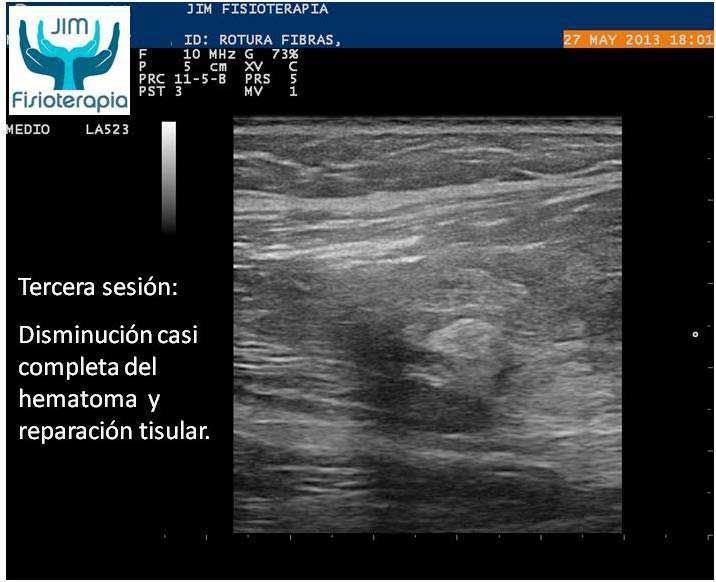

Se procede a la aplicación de EPI® con el fin de “vaporizar” el derrame producido y favorecer el proceso de regeneración y cicatrización muscular sin fibrosis. En las imágenes se puede apreciar el cambio en el tejido desde la primera sesión, fueron necesarias cuatro sesiones de EPI® hasta lograr la recuperación completa, a partir de la segunda sesión el paciente refirió una desaparición del dolor en la marcha y las actividades cotidianas, complementando su tratamiento con la aplicación de Radiofrecuencia.